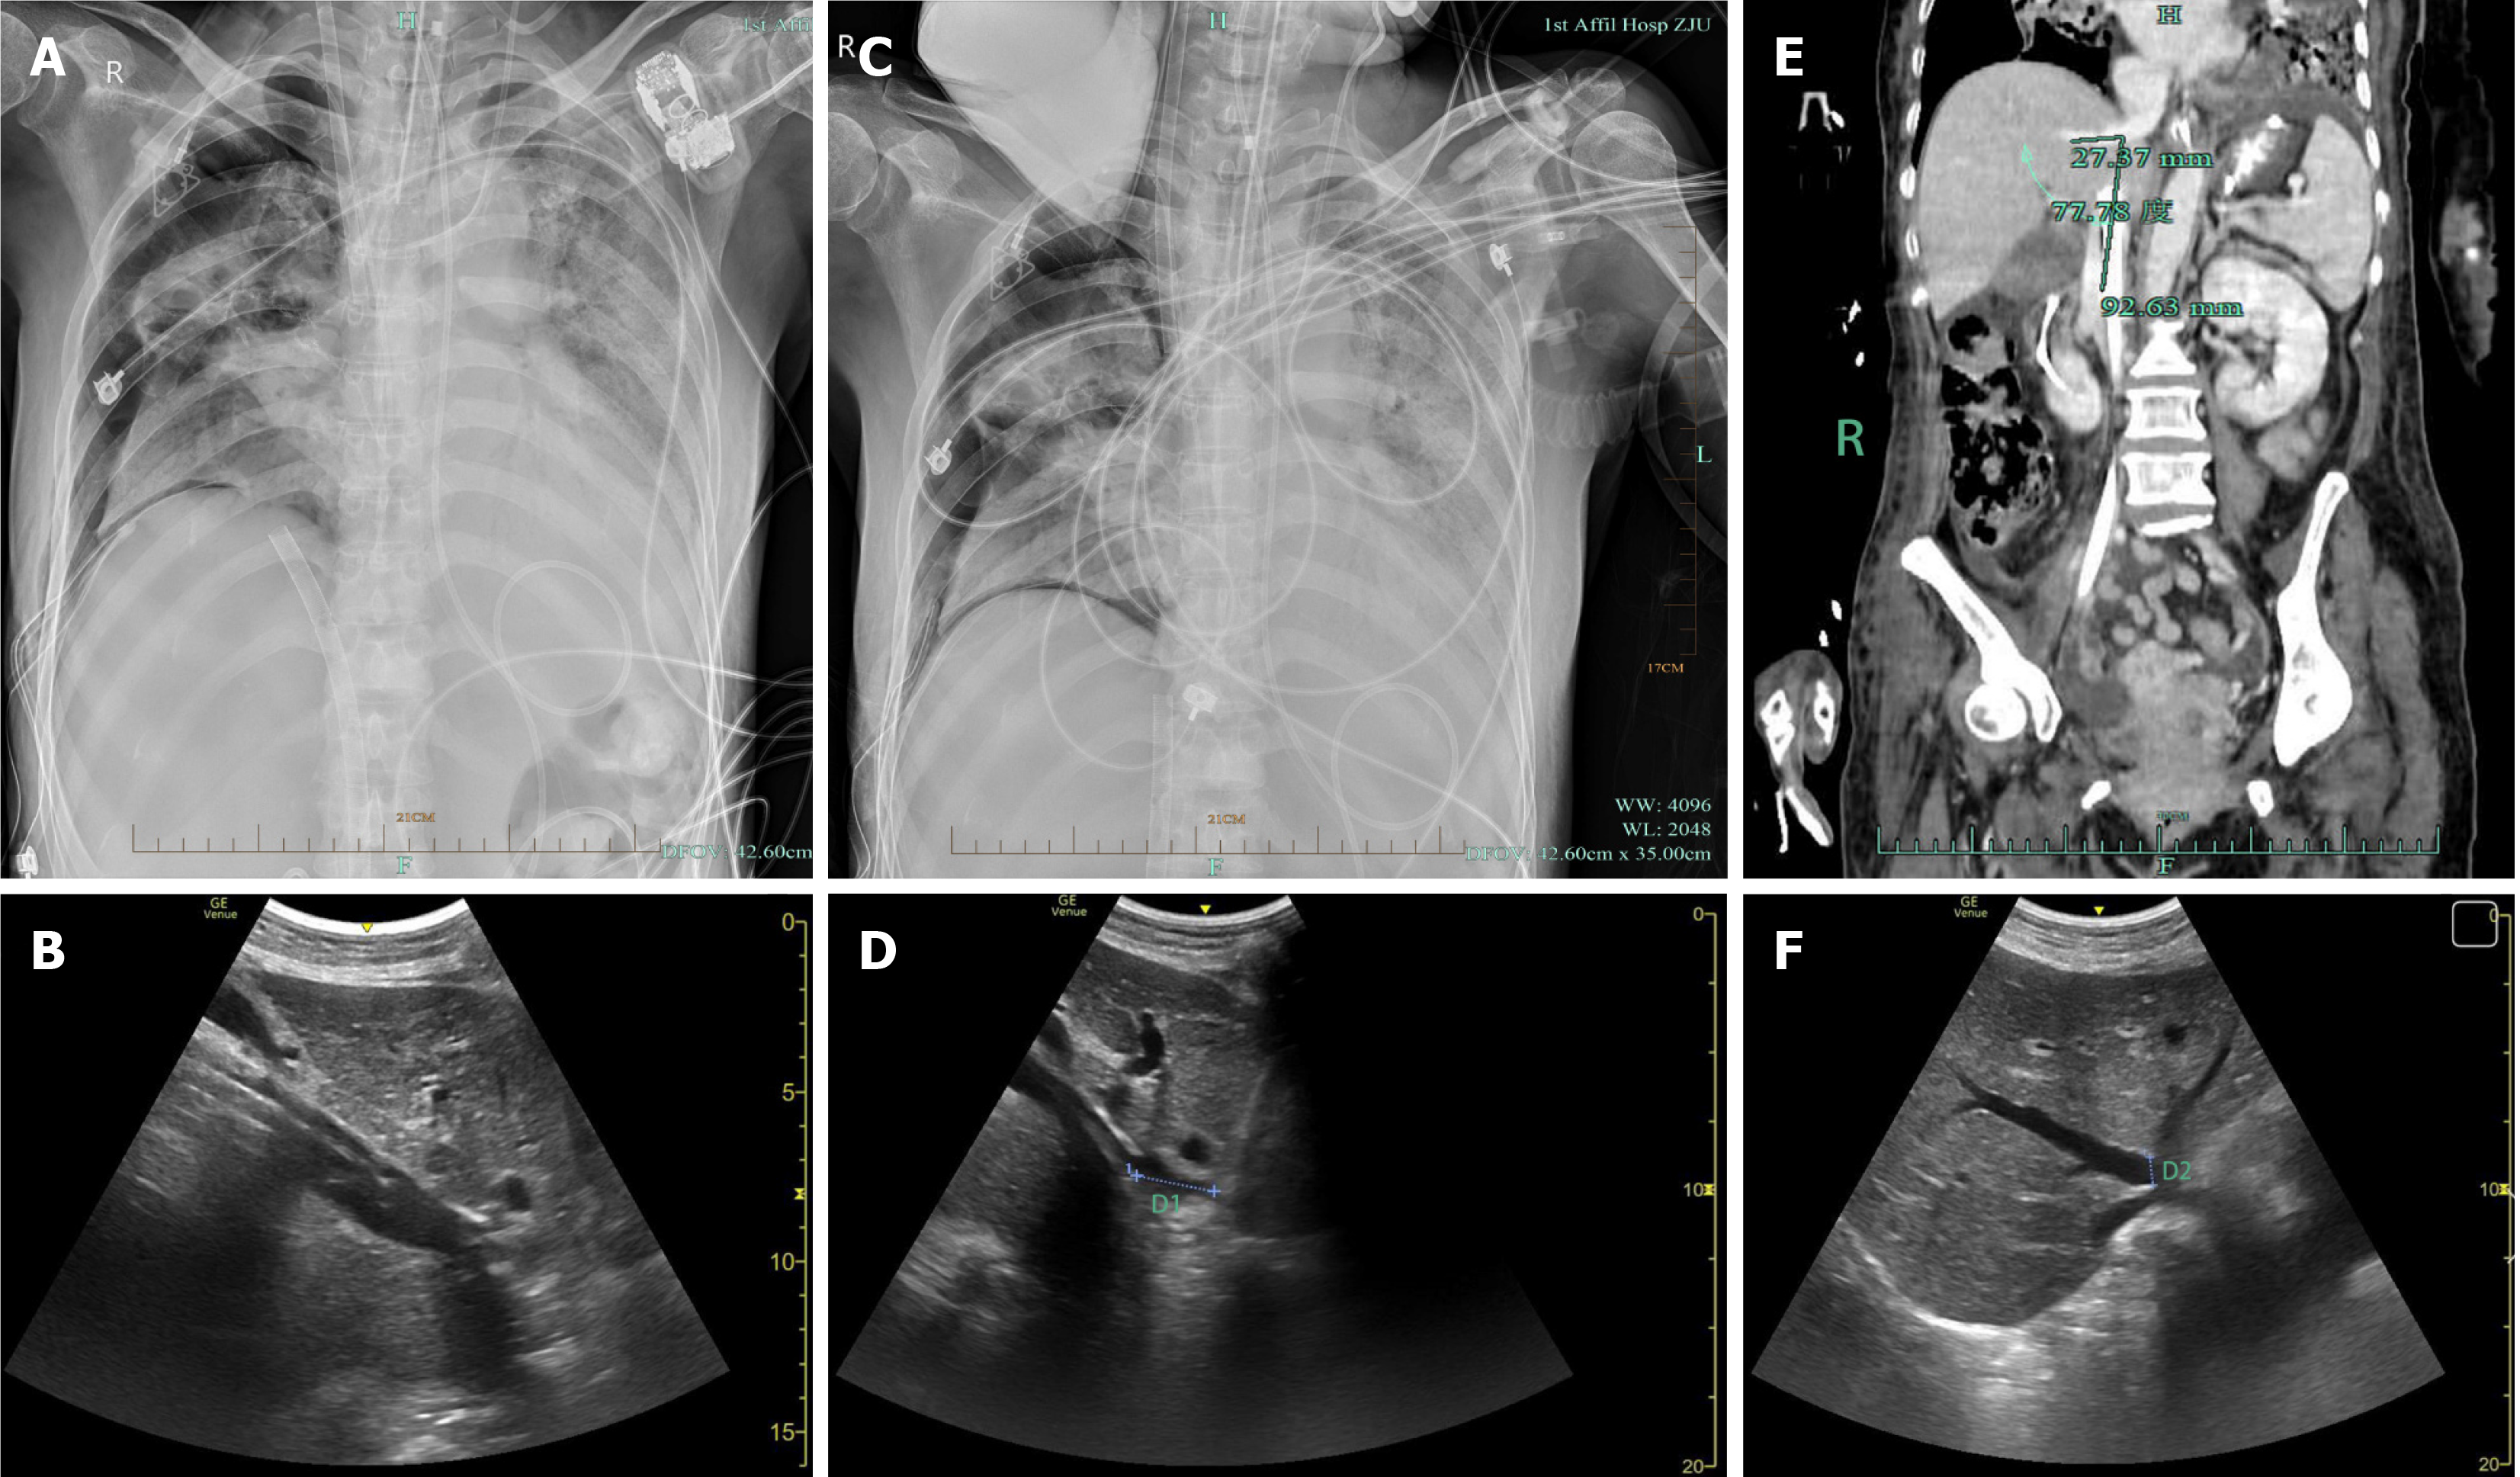

Several hours later, ECMO flow became unstable. Bedside radiography and ultrasonography revealed that the tip of the ECMO venous drainage cannula was misplaced in the middle HV instead of the IVC (Figure 1A and B). The ECMO team immediately initiated corrective action. After ultrasonography confirmed that there was no hepatic rupture, HV injury, or significant hemorrhage, the cannula was carefully withdrawn from the IVC under ultrasonographic guidance. To ensure optimal venous drainage and ECMO preloading, the cannula tip was advanced to the intended position at the junction of the IVC and RA. However, the cannula entered the middle HV again, forcing us to abandon further attempts. Finally, the cannula was placed at a depth of 36 cm, securing its position within the IVC, approximately 2.71 cm from the RA (Figure 1C and D).

After this adjustment, the ECMO parameters were recalibrated to a rotational speed of 3070 rpm, flow rate of 4.16 L/min, gas flow rate of 3 L/min, and oxygen concentration of 90% to stabilize the ECMO flow. Subsequent contrast-enhanced abdominal CT angiography and ultrasonography were performed to further assess the patient’s vascular anatomy. Additional imaging revealed a 77.78° angle between the middle HV and the IVC (Figure 1E) and an unusually wide opening of the middle HV, approximately 1.02 cm in diameter (Figure 1F). Fortunately, multiple subsequent evaluations did not reveal hepatic rupture, HV injury, or intra-abdominal hemorrhage (Figure 1E and F), and liver function was not significantly affected, with ALT at 11 U/L, AST at 21 U/L, total bilirubin at 21.5 μmol/L, and direct bilirubin at 10.1 μmol/L.